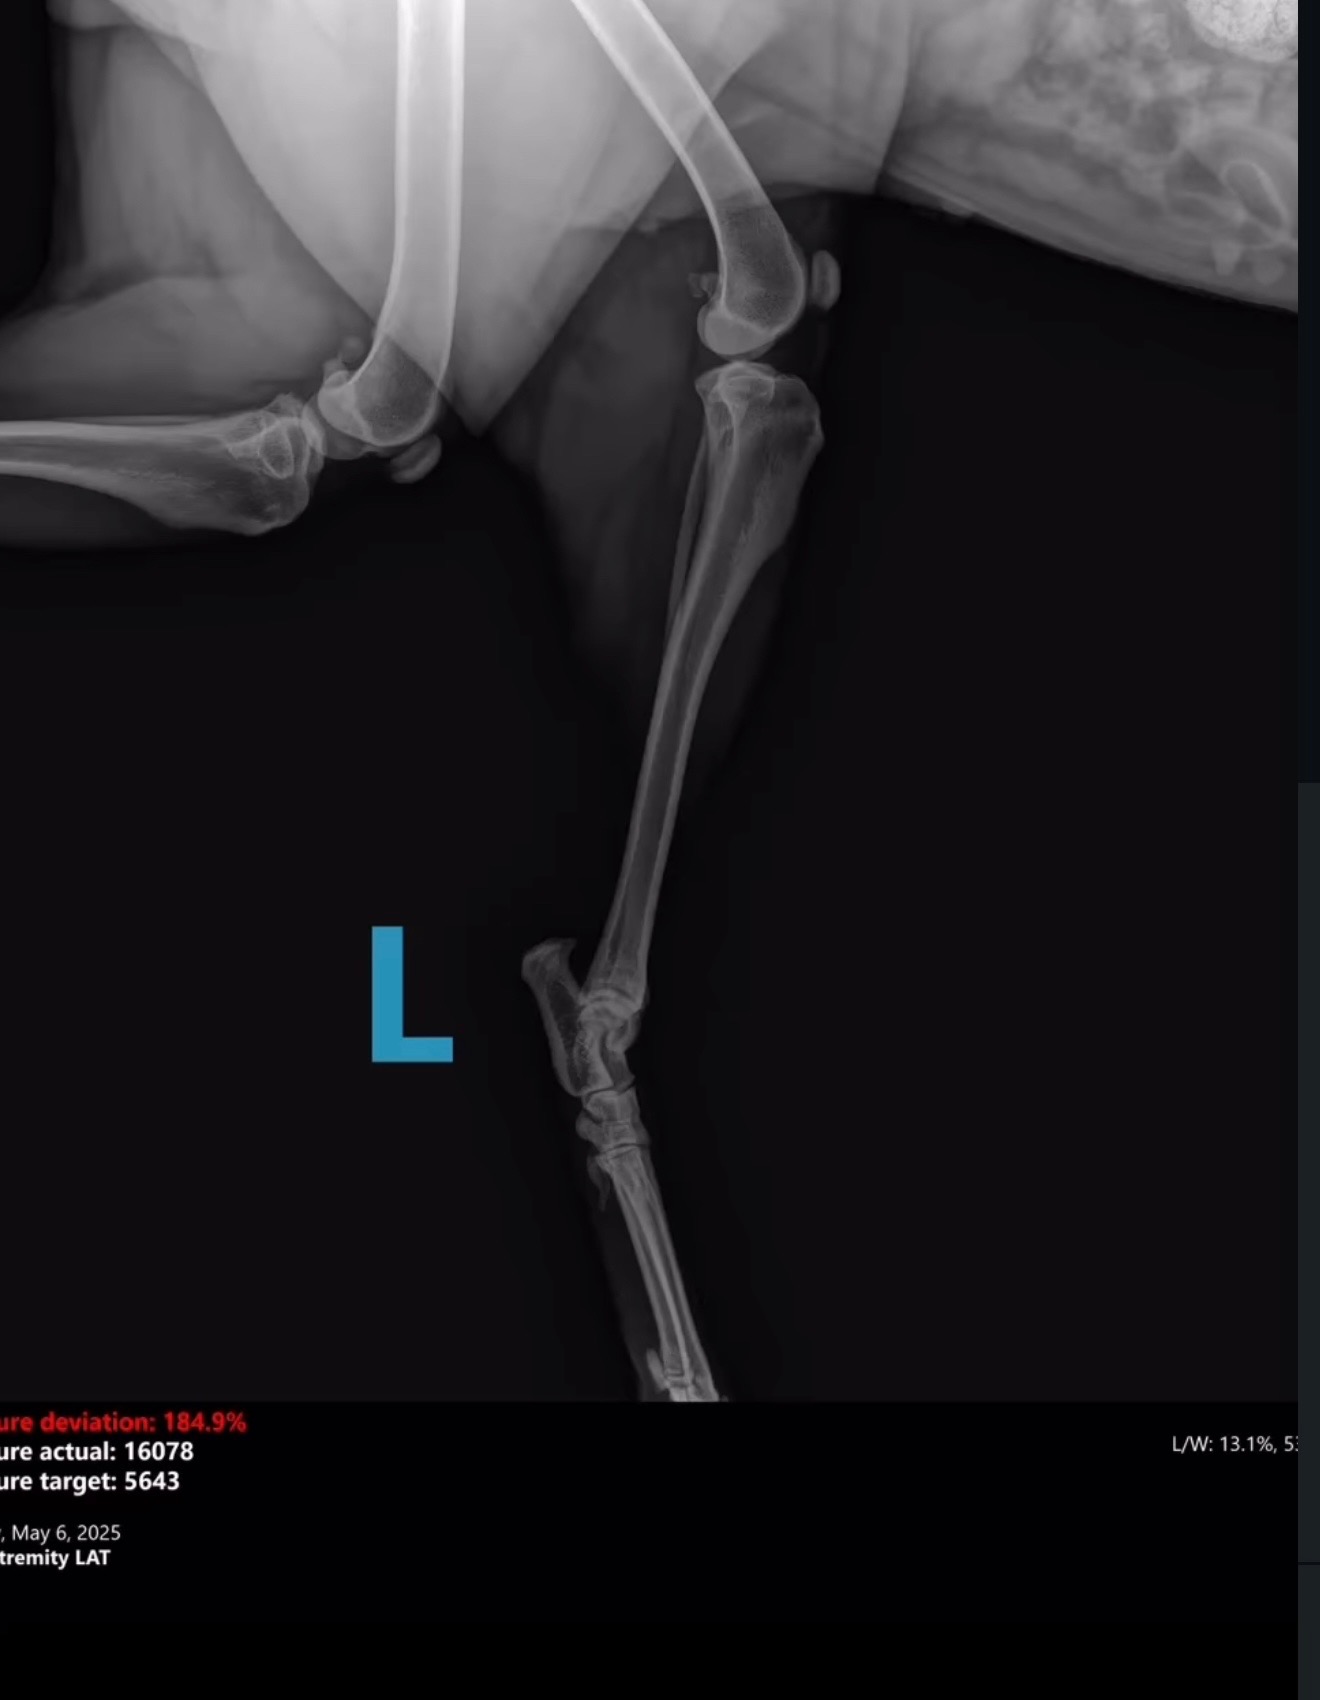

On Monday, a Good Samaritan found Harper in Dekalb County broken and in urgent need of medical attention. Unfortunately, their car broke down on the way to DCAS, and Gwinnett County kindly took her in. Harper arrived without a microchip and the shelter has been unable to locate an owner. We are unsure what caused her injuries exactly, but they are severe.

Harper has suffered multiple fractures on the left side

of her pelvis, including:

1. Left ischium

2. Left acetabulum

3. Crushed left ilial wing

4. Suspected fracture at the left sacroiliac (SI) joint

We’ve attached her kennel X-rays, and a short video to help you get to know her better.